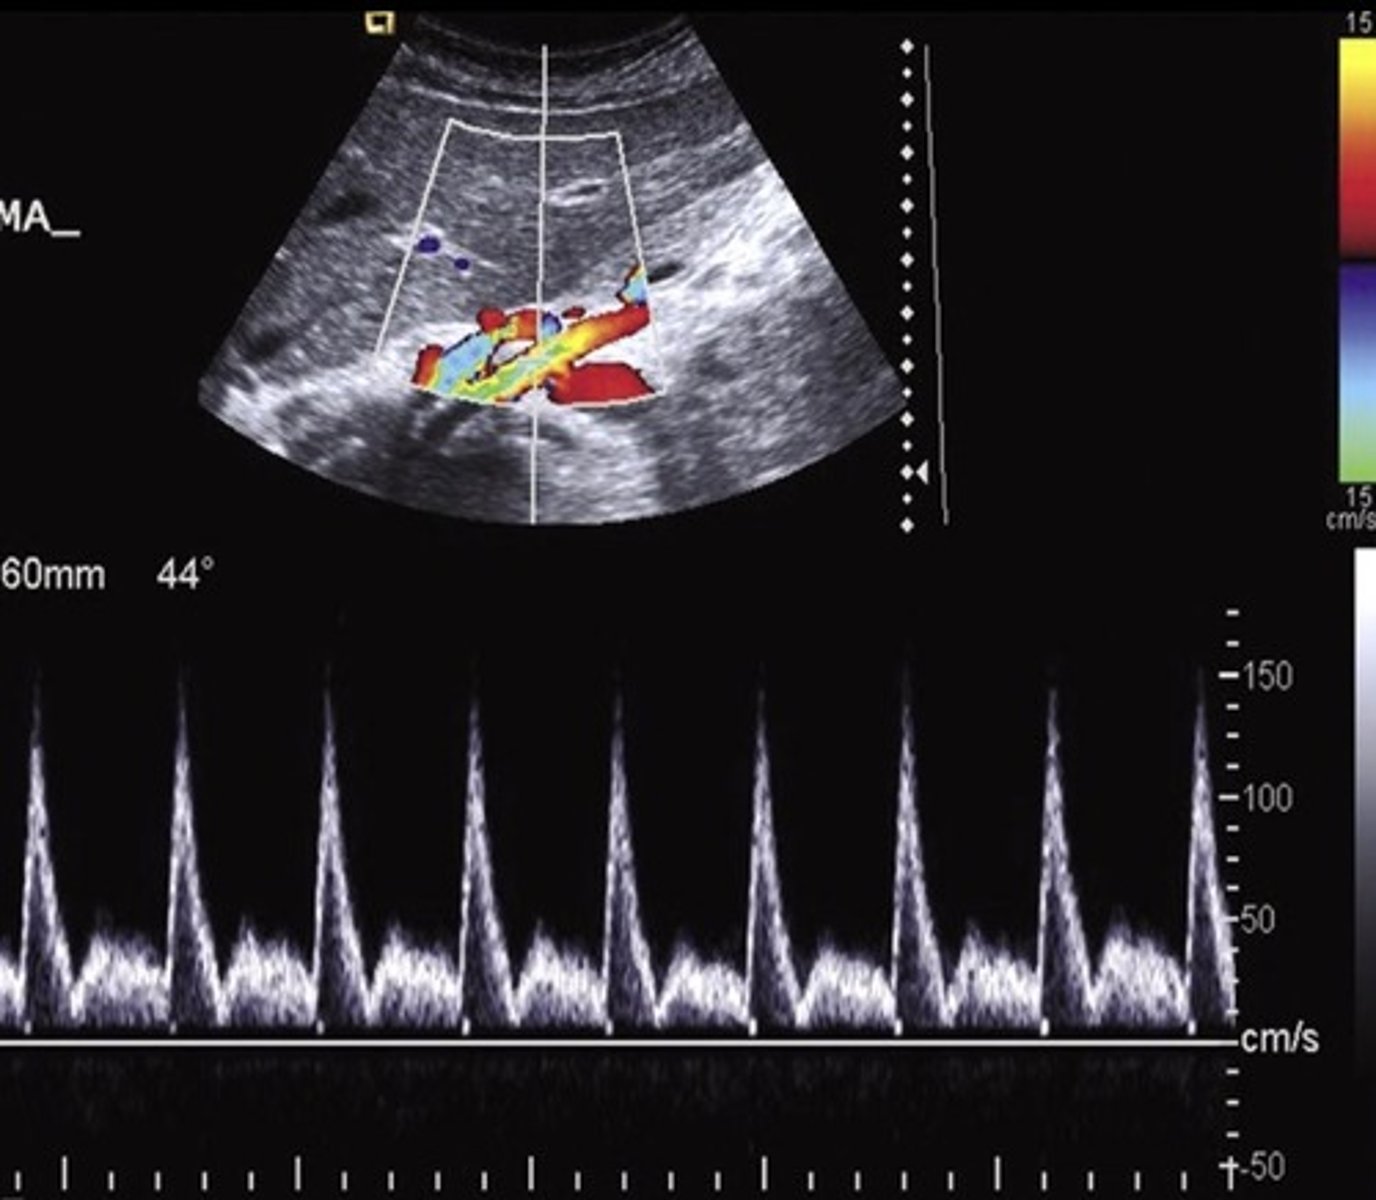

Pre-Prandial SMA Doppler

Post-Prandial SMA Doppler